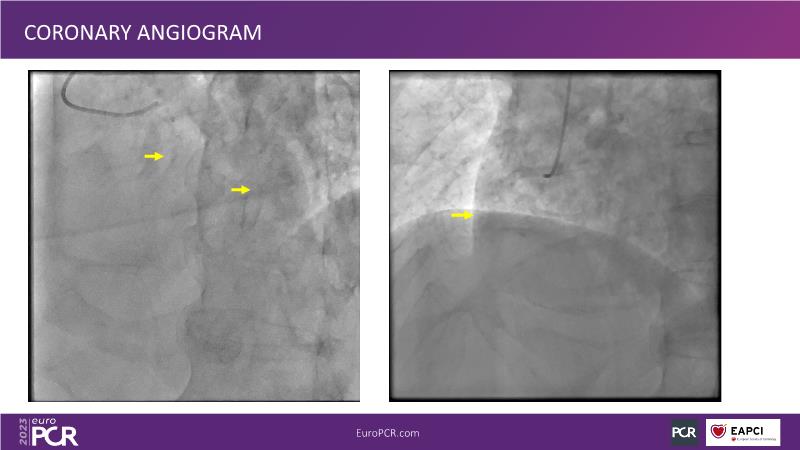

In this session focused on epicardial and microcirculatory dysfunction, discuss how to treat both a 72-year-old smoker man with HTN, diabetes, hyperlipidemia, who presented with angina and dyspnea with moderate exertion over the last months, and a 69-year-old ex-smoker man with HTN and untreated LDL 125 mg/dl who presented with chest pain of unknown origin started about 6 months ago and shortness of breath on exertion.

- To understand the value of intravascular physiology to guide your management of epicardial disease